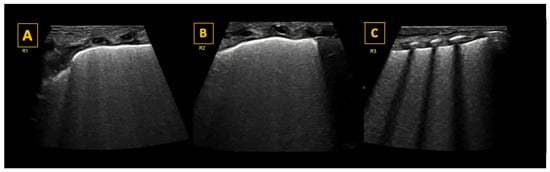

- (A)

- Respiratory Distress Syndrome

- (B)

- Meconium Aspiration Syndrome (MAS)

- (C)

- Transient Tachypnea of Newborn (TTN)

- (D)

- Pneumothorax

| Lung Pathology | Lung Sliding | A-Lines | B-Lines | Consolidation | M-Mode | Other Signs | ||

|---|---|---|---|---|---|---|---|---|

| Microconsolidations <5 mm | >5 mm | |||||||

| Normal lung | ![]() | Present | Yes | <3/intercostal space | No | No | Seashore sign | Lung pulse may be present |

| RDS | ![]() | Present | No (minimal) | >3/intercostal space Confluent “White lung” | Usual | Unusual | Seashore sign | No “spared” areas |

| TTN | ![]() | Yes | Yes | Yes | Sometimes | Unusual | Seashore sign | “Spared areas” Double lung point in approximately 50% of cases |

| Pneumothorax | ![]() | Absent | Yes | No | No | No | Stratosphere sign | The lung point confirms diagnosis |

| Meconium aspiration syndrome | ![]() | Variable | Variable | Yes | Yes/no | Yes | Seashore sign | Multiple consolidations usual |